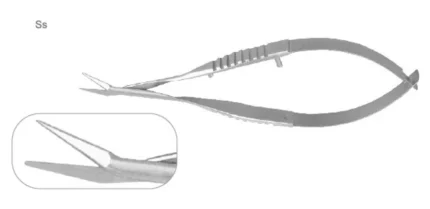

Главная / Каталог / Инструменты / Ножницы / НОЖНИЦЫ МИКРОХИРУРГИЧЕСКИЕ IRIDECTOMY SCISSORS М 103.2; М 103.3; М 103.4; М 103.7 (23)

НОЖНИЦЫ МИКРОХИРУРГИЧЕСКИЕ IRIDECTOMY SCISSORS М 103.2; М 103.3; М 103.4; М 103.7 (23)

«NOYES»

бранши плоские,

ширина бранш 7,8 мм

длина лезвия 22,5 мм

длина общая 118 мм